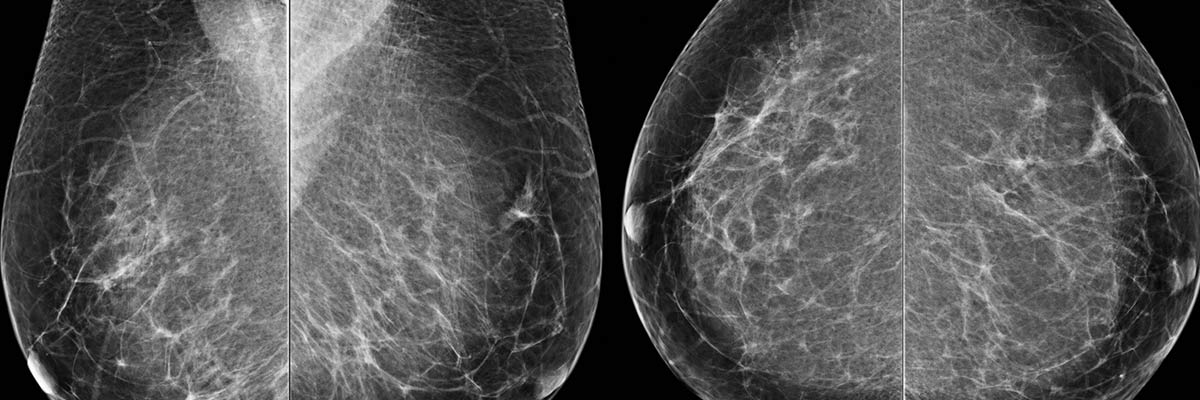

At DRCTC, our digital mammography system produces high- quality images that allow for better visualization of breast tissue, aiding in the early detection of breast cancer. Early detection has been shown to dramatically increase the survival rates of women afflicted with this deadly disease.

The Siemens is a state-of-the-art breast cancer detection system designed to improve the quality and comfort of mammograms. This advanced system offers physicians precise viewing options that were never possible with conventional film.

A physician can zoom in, magnify and optimize different parts of the breast tissue, enhancing readability and interpretation of the images. Plus, the images can be sent anywhere in the world to be viewed by another physician.

Compared to conventional film, digital images give better visibility of the breast, particularly near the skin line and chest wall. Theyre ideal for women with implants. For women with dense breast tissue, digital is far superior and may involve less radiation than a standard mammography.

In addition, digital exams usually take less than half the time of traditional exams and result in a 20 to 30 percent reduction in callbacks.

Mammography exams are also performed at our Fort Pierce location and take approximately 20 minutes.